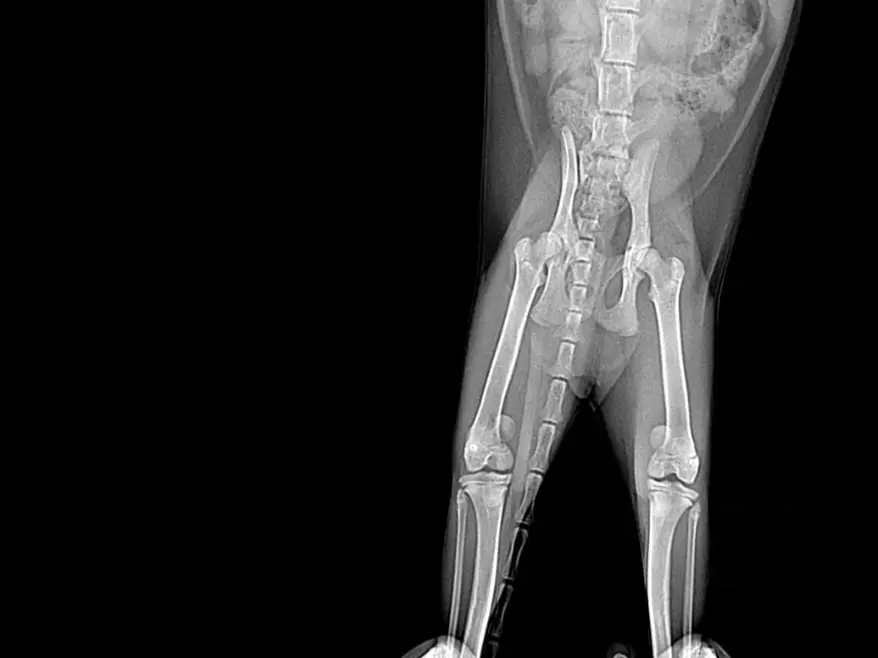

В ветклинике сообщили шокирующую новость — у малышки врожденный вывих коленных суставов. Если его вовремя не лечить, лапка может неправильно работать, болеть, разрушиться и котенок будет плохо себя чувствовать.

На днях малышу провели первая операция, начали с лапы посложнее. Операция прошла штатно, После Нового года котенку проведут еще одну дорогостоящую операцию.